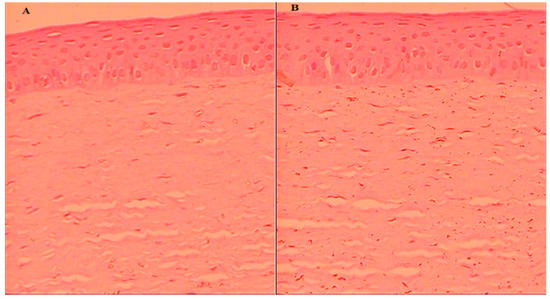

2.8.6. Histopathology

The cornea was collected after the permeation study and assessed for internal damage in the structure. The histopathology of the treated cornea with AM-NLopIG and control (NaCl, 0.9%) was compared to changes in the structure, as depicted in Figure 7A,B. AM-NLopIG-treated cornea revealed no marked change in the internal structure. No damage in cellular structure or histological alterations were observed in the treated cornea, matching with the normal saline-treated cornea. The epithelium, Bowman’s membrane, and stroma of the cornea and the cells were found intact, similar to the control sample. The morphology of the cornea was also well maintained [38]. From the results, we can presume that there is no alteration in the corneal structure, and that AM-NLopIG is nontoxic and compatible with the ocular structure.

6.11. Histopathology Study

The histopathology of the cornea was evaluated to check the internal damage after treatment with a prepared formulation. The cornea was collected after the permeation study, washed with STF, and stored in formalin solution (10% v/v.) The cornea was treated with 0.9% NaCl solution taken as a control. Each treated cornea was cleaned with alcohol and mounted with molten paraffin. The cross-section of the cornea was cut and stained with hematoxylin and eosin to evaluate under a high-resolution microscope (BA210m Motic microscope, Selangor Darul Ehsan, Malaysia).

Figure 7. Histopathology image of AM-NLopIG-treated cornea (A). NaCl-treated cornea (B) taken by light microscope at image scale 40×.